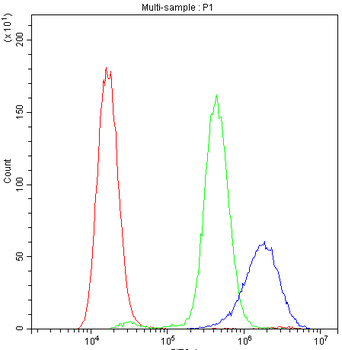

Anti-Cyclophilin A/PPIA Antibody [orb19174]

FC, ICC, IF, IHC, IHC-Fr, WB

Human, Mouse, Rat

Rabbit

Polyclonal

Unconjugated

10 μg, 100 μgCYPA Rabbit Polyclonal Antibody [orb100498]